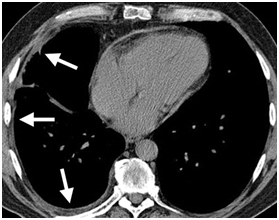

Figure 3: Pulmonary hypertension in a 27-year-old woman with progressive systemic sclerosis. Unenhanced axial CT image depicts enlargement of the pulmonary artery (PA) trunk and a substantial amount of pericardial effusion (arrows) in the anterior superior aortic recess.

https://s3-us-west-2.amazonaws.com/typeset-media-server/4cf22ff2-6474-4d74-8b88-d617847826caimage5.png